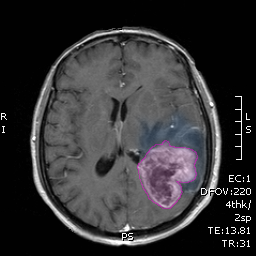

Κατάλληλοι για χειρουργική αξιολόγηση είναι όλοι ανεξαιρέτως οι ασθενείς με αποδεδειγμένη απεικονιστικά χωροκατακτητική εξεργασία του εγκεφάλου. Αυτό συμπεριλαμβάνει όχι μόνο ασθενείς με συμπτώματα αλλά και ασθενείς στους οποίος η εξεργασία είναι τυχαίο εύρημα σε απεικονιστική εξέταση για άλλους λόγους (όπως πχ μια κρανιοεγκεφαλική κάκωση). Θα πρέπει εδώ να σημειωθεί ότι όλες οι απεικονιζόμενες βλάβες του εγκεφάλου δεν είναι σε καμία περίπτωση όγκοι, κάποιες είναι λοιμώδους, νευροεκφυλιστικής ή άλλης προέλευσης. Η εξεργασία αξιολογείται όσον αφορά τα απεικονιστικά της χαρακτηριστικά (θέση, μέγεθος, στην περίπτωση των πολλαπλών εξεργασιών αριθμός, σχέση με ζωτικά ή ευγενή κέντρα του εγκεφάλου, αγγεία, κρανιακά νεύρα κα)και γίνεται μια πρώτη εκτίμηση για την προέλευση και την άμεση επικινδυνότητά της. Η εκτίμηση αυτή γίνεται κλινικά (ιστορικό, κλινική εξέταση) και με μελέτη της απεικόνισης η οποία πρέπει να είναι μαγνητική τομογραφία με σκιαγραφικό-εκτός των περιπτώσεων που αυτή αντενδείκνυται.

Χονδρικά οι όγκοι του εγκεφάλου διακρίνονται σε πρωτοπαθείς και δευτεροπαθείς. Οι πρώτοι προέρχονται από ιστούς του κεντρικού νευρικού συστήματος (νευρώνες, μήνιγγες, νευρογλοιακά κύτταρα κα) και οι δευτεροπαθείς προέρχονται από άλλα όργανα και ονομάζονται επίσης μεταστατικοί. Η απεικόνιση του εγκεφάλου ενδέχεται να μην επαρκεί για αυτόν τον διαχωρισμό-όπως σε ασθενείς με μονήρεις μεταστατικές βλάβες ή με αδιάγνωστη πρωτοπαθή εστία- και ενδέχεται να χρειάζεται να συμπληρωθεί με επιπλέον απεικονίσεις των συχνότερων εστιών πρωτοπαθών νεοπλασμάτων (πνεύμονας, μαστοί, θυρεοειδής κα) καρκινικούς δείκτες ή άλλες εξετάσεις.

Σκοπός της συνολικής αξιολόγησης είναι να διαπιστωθεί η ανάγκη χειρουργικής επέμβασης, τα χρονικά πλαίσια στα οποία πρέπει να πραγματοποιηθεί, η έκταση της και τα δυνητικά οφέλη της σε σχέση με τους κινδύνους της. Η τελευταία παράμετρος είναι εξαιρετικά σημαντική και εξατομικευμένη καθ' όσον ορισμένες, κυρίως πρωτοπαθείς, βλάβες διηθούν περιοχές του εγκεφάλου που ελέγχουν την κίνηση, τον λόγο ή άλλες ανώτερες νοητικές λειτουργίες και η εξαίρεσή τους μπορεί να σημαίνει νευρολογικό λειτουργικό έλλειμμα.